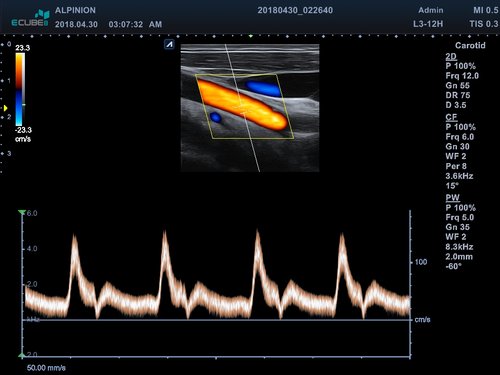

• PW-Doppler (Pulsed-Wave): Verfahren, das ein Geschwindigkeitsspektrum von beweglichem Gewebe und Flüssigkeiten an einer bestimmten Position liefert

• Farbdoppler: farbige Darstellung der Richtung des Blutflusses

• L3-12T (3-12 MHz) für Ultraschalluntersuchungen in Bereichen Brust, Notfallmedizin, MSK, Vaskulär, Kleine Organe, Appendix